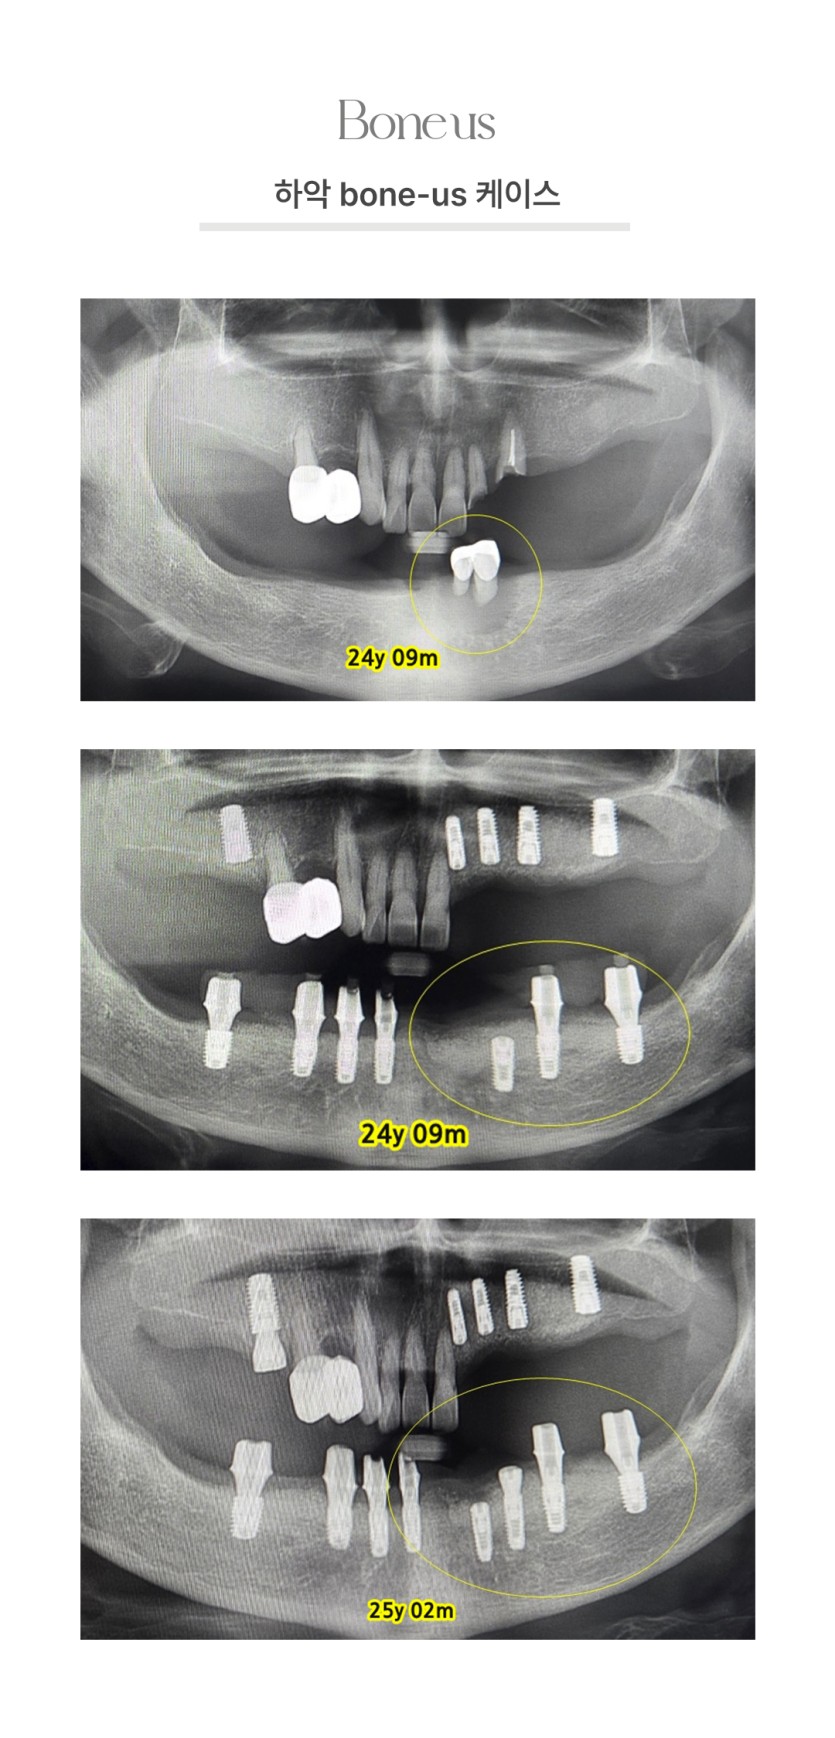

CLINICAL CASE

본어스 시술사례

하악 본어스 케이스 2

하악 본어스 케이스 3

하악 본어스 케이스 1